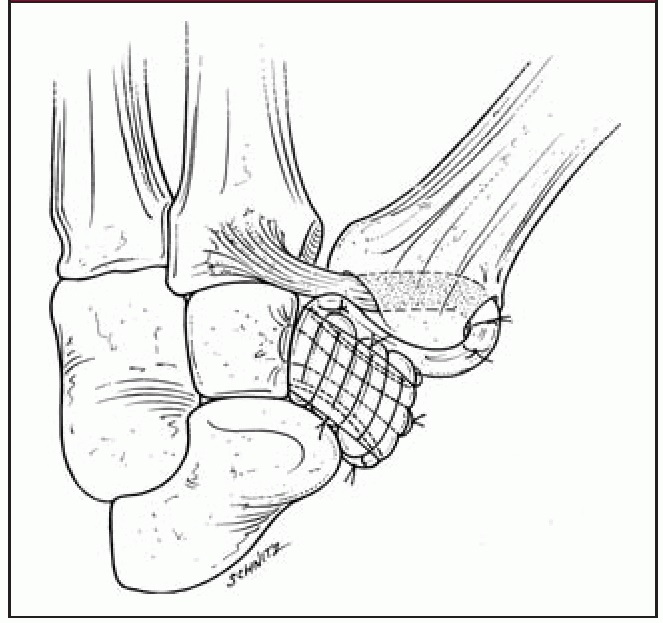

• Harvesting a tendon from the wrist and weaving it through a drill hole in the metacarpal to hold it up (LRTI)

Diagram of a thumb CMC arthroplasty procedure with removal of the trapezium and use of a wrist tendon (FCR) to suspend the thumb metacarpal (LRTI).

Reproduced from Van Heest AE, Kallemeier P. Thumb Carpal Metacarpal Arthritis. J Am Acad Orthop Surg 2008;16(3):140-151. Reproduced with permission from Burton R: Resection/suspension arthroplasty of the basal joint of the thumb for osteoarthritis, in Strickland JW [ed]: The Hand. Philadelphia, PA: Lippincott-Raven 1998;p 455.